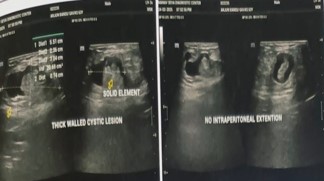

A 63-year-old male, farmer by occupation, presented with complaints of painful, irreducible, swelling in supra-umblical region since past four days. Both the symptoms observed simultaneously after lifting heavy weight. Pain was persistent, localized over the swelling and has mild to moderate in intensity. It was not associated with fever, vomiting, abdominal distension, constipation or obstipation. Patient did not have any history of previous abdominal surgery or ventral hernias. General physical examination was unremarkable. Abdominal examination revealed a 6 cm × 4 cm, well defined, firm, globular and tender swelling in mid-line just above the umbilicus (Figures 1a & 1b). There was no local rise of temperature and skin over the swelling was normal. Rest of the abdomen was scaphoid, nondistended, soft, nontender and bowel sounds were normal over all four quadrants of abdomen. Urgent laboratory investigation revealed leucocytosis (TLC12000/Cmm) with Neutrophil count of 80%. Other haematological and bio-chemical parameters were within normal limits. There was no dilated bowel loops, abnormal air-fluid levels or gas under diaphram on X-Ray chest and abdomen. Ultrasound abdomen, done at an outside centre, showed an extra-peritoneal cystic mass (Figure 2) without intraperitoneal extension, repeat ultrasound at our centre revealed a 13.6 mm size defect in anterior abdominal wall in supra-umbilical region with herniation of omentum and anechoic fluid collection in hernial sac suggestive of irreducible para-umblical hernia with omentocoele. In view of clinicoradiological suspicion of complicated ventral hernia, patient was taken up for emergency exploration under general anaesthesia via supraumblical mid-line incision. A ventral defect of approx 1.5 cm size was noticed in mid-line through which a cystic swelling of 6 cm × 5 cm was found protruding out which was attached to the ileum with a fibrous band (Figures 3a & 3b). The size of ventral defect was increased to deliver the content which was found attached to ileum with a fibrous band. The cyst along with its band was carefully dissected off the bowel, specimen (Figure 3c) was sent for histo-pathological examination, bowel was replaced back into the peritoneal cavity and ventral defect was repaired using nonabsorbable suture. Post op period was uneventful, patient was started on orals in the evening of surgery, discharged on 3rd post operative day and skin sutures were removed after ten days. Histopathological examination of specimen was reported as a unilocular cyst cavity lined by mesenteric type epithelium. The lining epithelium was surrounded by fibro-fatty tissue with psammoma bodies suggestive of OMD cyst (Figures 4a & b).

Figure 2: Ultrasonography abdomen – (A) Thick-walled lesion with solid and cystic component without intra-peritoneal extension.